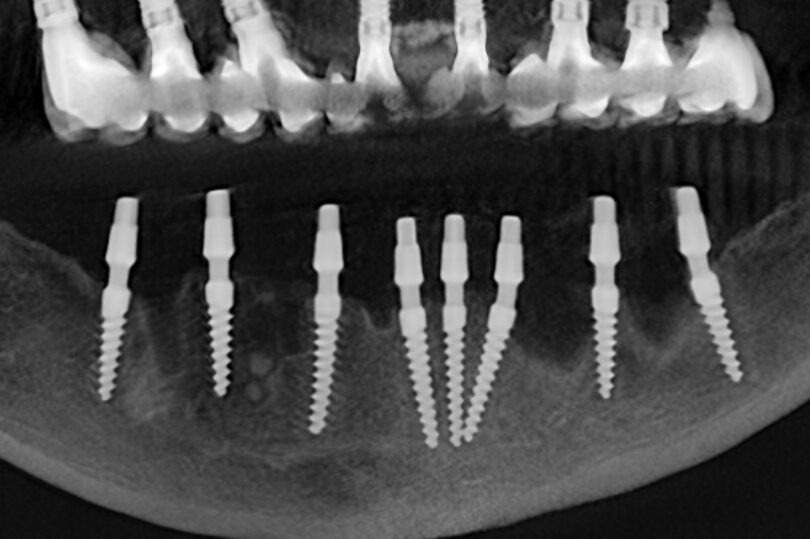

🦷 Antes, durante y después: así mejoró este caso de periimplantitis en 2 años 🦷